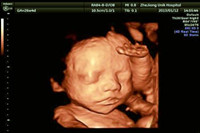

孕期里最重要的檢查就是B超檢查了,說(shuō)起四維彩超的好處那真的是數(shù)不勝數(shù)。下面,就讓我們一起通過(guò)以下的,【雙胞胎四維彩超圖片】來(lái)進(jìn)行了解,文中還會(huì)告訴你,雙胞胎做四維彩超的最...

四維彩超它是目前最先進(jìn)的彩超設(shè)備,說(shuō)起四維彩超的功能和作用,相信只要是懷孕過(guò)的媽媽們一定都十分清楚,四維彩超不僅可以檢測(cè)篩查胎兒畸形,而且它還可以很全面的檢測(cè)出寶...